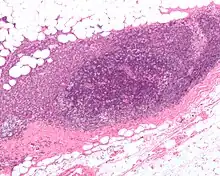

To perform a sentinel lymph node biopsy, the physician performs a lymphoscintigraphy, wherein a low-activity radioactive substance is injected near the tumor. The injected substance, filtered sulfur colloid, is tagged with the radionuclide technetium-99m. The injection protocols differ by doctor but the most common is a 500 μCi dose divided among 5 tuberculin syringes with 1/2 inch, 24 gauge needles. In the UK 20 megabecquerels of nanocolloid is recommended.[8] The sulphur colloid is slightly acidic and causes minor stinging. A gentle massage of the injection sites spreads the sulphur colloid, relieving the pain and speeding up the lymph uptake. Scintigraphic imaging is usually started within 5 minutes of injection and the node appears from 5 min to 1 hour. This is usually done several hours before the actual biopsy. About 15 minutes before the biopsy the physician injects a blue dye in the same manner. Then, during the biopsy, the physician visually inspects the lymph nodes for staining and uses a gamma probe or a Geiger counter to assess which lymph nodes have taken up the radionuclide. One or several nodes may take up the dye and radioactive tracer, and these nodes are designated the sentinel lymph nodes. The surgeon then removes these lymph nodes and sends them to a pathologist for rapid examination under a microscope to look for the presence of cancer.

A frozen section procedure is commonly employed (which takes less than 20 minutes), so if neoplasia is detected in the lymph node a further lymph node dissection may be performed. With malignant melanoma, many pathologists eschew frozen sections for more accurate "permanent" specimen preparation due to the increased instances of false-negative with melanocytic staining.